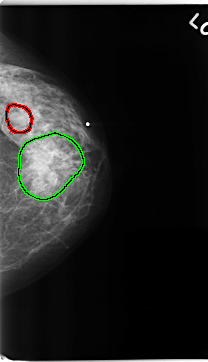

C_0229_1.LEFT_CC

FILE: C_0229_1.LEFT_CC.OVERLAY

TOTAL_ABNORMALITIES 2

ABNORMALITY 1

LESION_TYPE MASS SHAPE OVAL MARGINS CIRCUMSCRIBED

ASSESSMENT 3

SUBTLETY 5

PATHOLOGY BENIGN

TOTAL_OUTLINES 1

BOUNDARY

ABNORMALITY 2

LESION_TYPE MASS SHAPE IRREGULAR MARGINS SPICULATED

ASSESSMENT 5

PATHOLOGY MALIGNANT